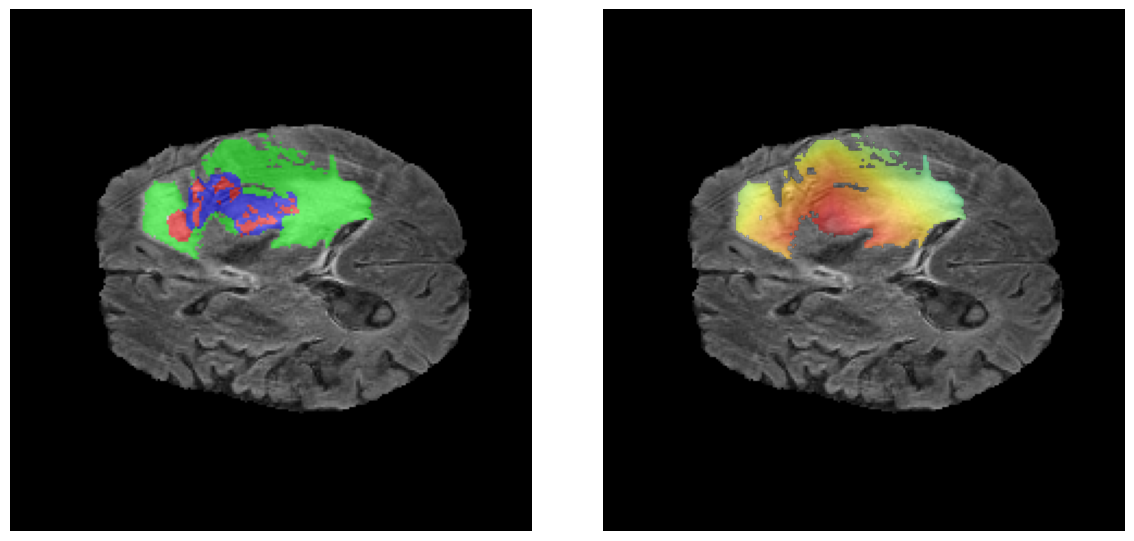

Mapas de Explicabilidad (Grad-CAM++)

Visualización de las regiones de atención del modelo que validan su razonamiento clínicamente relevante

Ejemplos HGG - Atención en Núcleo Necrótico y Tumor Realzado

HGG Grad-CAM++ 1 HGG Grad-CAM++ 2 HGG Grad-CAM++ 3 HGG Grad-CAM++ 4 HGG Grad-CAM++ 5 HGG Grad-CAM++ 6

Los heatmaps muestran que el modelo concentra su atención en las regiones de Tumor Realzado (rojo) y Núcleo Necrótico (azul), características patológicas clave de los gliomas de alto grado.

Ejemplos LGG - Atención Difusa en Edema Peritumoral

LGG Grad-CAM++ 1 LGG Grad-CAM++ 2 LGG Grad-CAM++ 3 LGG Grad-CAM++ 4 LGG Grad-CAM++ 5 LGG Grad-CAM++ 6

Para casos LGG, la atención del modelo es más difusa y se concentra principalmente en la región de Edema Peritumoral (verde), consistente con la naturaleza más infiltrativa y menos agresiva de estos tumores.

Validación con IA Explicable

El análisis Grad-CAM++ reveló que el modelo desarrolla automáticamente la capacidad de localizar las regiones tumorales. Para casos HGG, la atención se alinea fuertemente con las regiones de Tumor Realzado (ET) y Núcleo Necrótico (NCR). En contraste, los casos LGG muestran atención más difusa, principalmente concentrada en la región de Edema Peritumoral (ED), lo cual es consistente con la patofisiología conocida de los gliomas.

✅ Validación con IA Explicable

💡 Aprendizaje Autónomo de Localización

El modelo, entrenado únicamente con etiquetas de clasificación a nivel de imagen (HGG/LGG), desarrolló automáticamente la capacidad de localizar las regiones tumorales sin supervisión explícita de segmentación. Este es un hallazgo significativo que demuestra capacidades emergentes del deep learning.

✅ Razonamiento Clínicamente Coherente

La validación cuantitativa confirmó que las predicciones del modelo se basan en sub-regiones biológicamente relevantes (Núcleo Necrótico y Tumor Realzado para HGG; Edema Peritumoral para LGG), alineándose con el conocimiento patológico establecido.